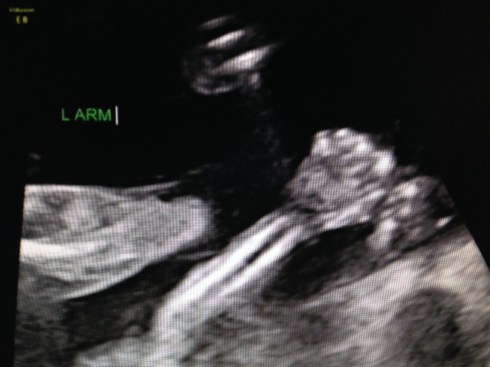

The ultrasound was performed on Friday, March 21, 2014 (at 19 weeks + 4 days). Our boy appeared healthy in all ways and weighed about 10 oz. His growth measurements were between 43% and 62% for his gestational age, and the heart rate was 147 bpm. The placenta is posterior and without previa. My cervix is long. Excellent!

We received a DVD of the scan. I took this short video clip with my phone, that shows baby’s face: moving his jaw, yawning, moving his tongue, and even smiling. You can also see his forearm in front of his face. Watch it again and look for the heart beating. Precious!!

I took these images by pausing the DVD and taking screen shots: